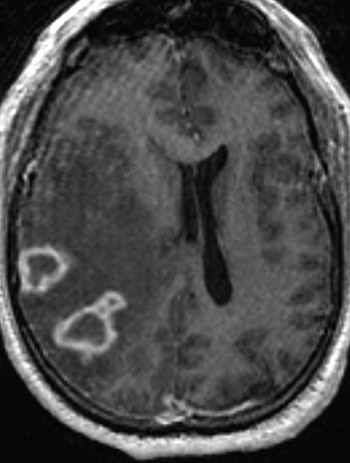

| This axial view MRI scan demonstrates tuberculomas in the right hemisphere which have central lucency from caseous necrosis and a brightly enhancing, somewhat irregular border from granulomatous inflammation. There is prominent adjacent edema producing marked effacement of the lateral ventricles on the right. |